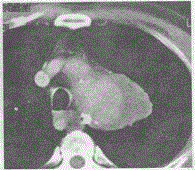

问题 男,65岁,突发胸痛3天,增强后如图,最可能的诊断是

选项 A.主动脉夹层 B.畸胎瘤 C.假性动脉瘤 D.动脉瘤 E.心包囊肿

答案 C